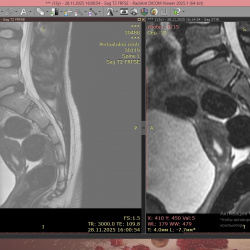

Здравствуйте, подскажите пациент 60 лет, особо жалоб нет, на узи было изменения в печени, в хвосте поджелудочной железы отмечаются немного гиподенсивные изменения может ли это быть раком? на МРТ...